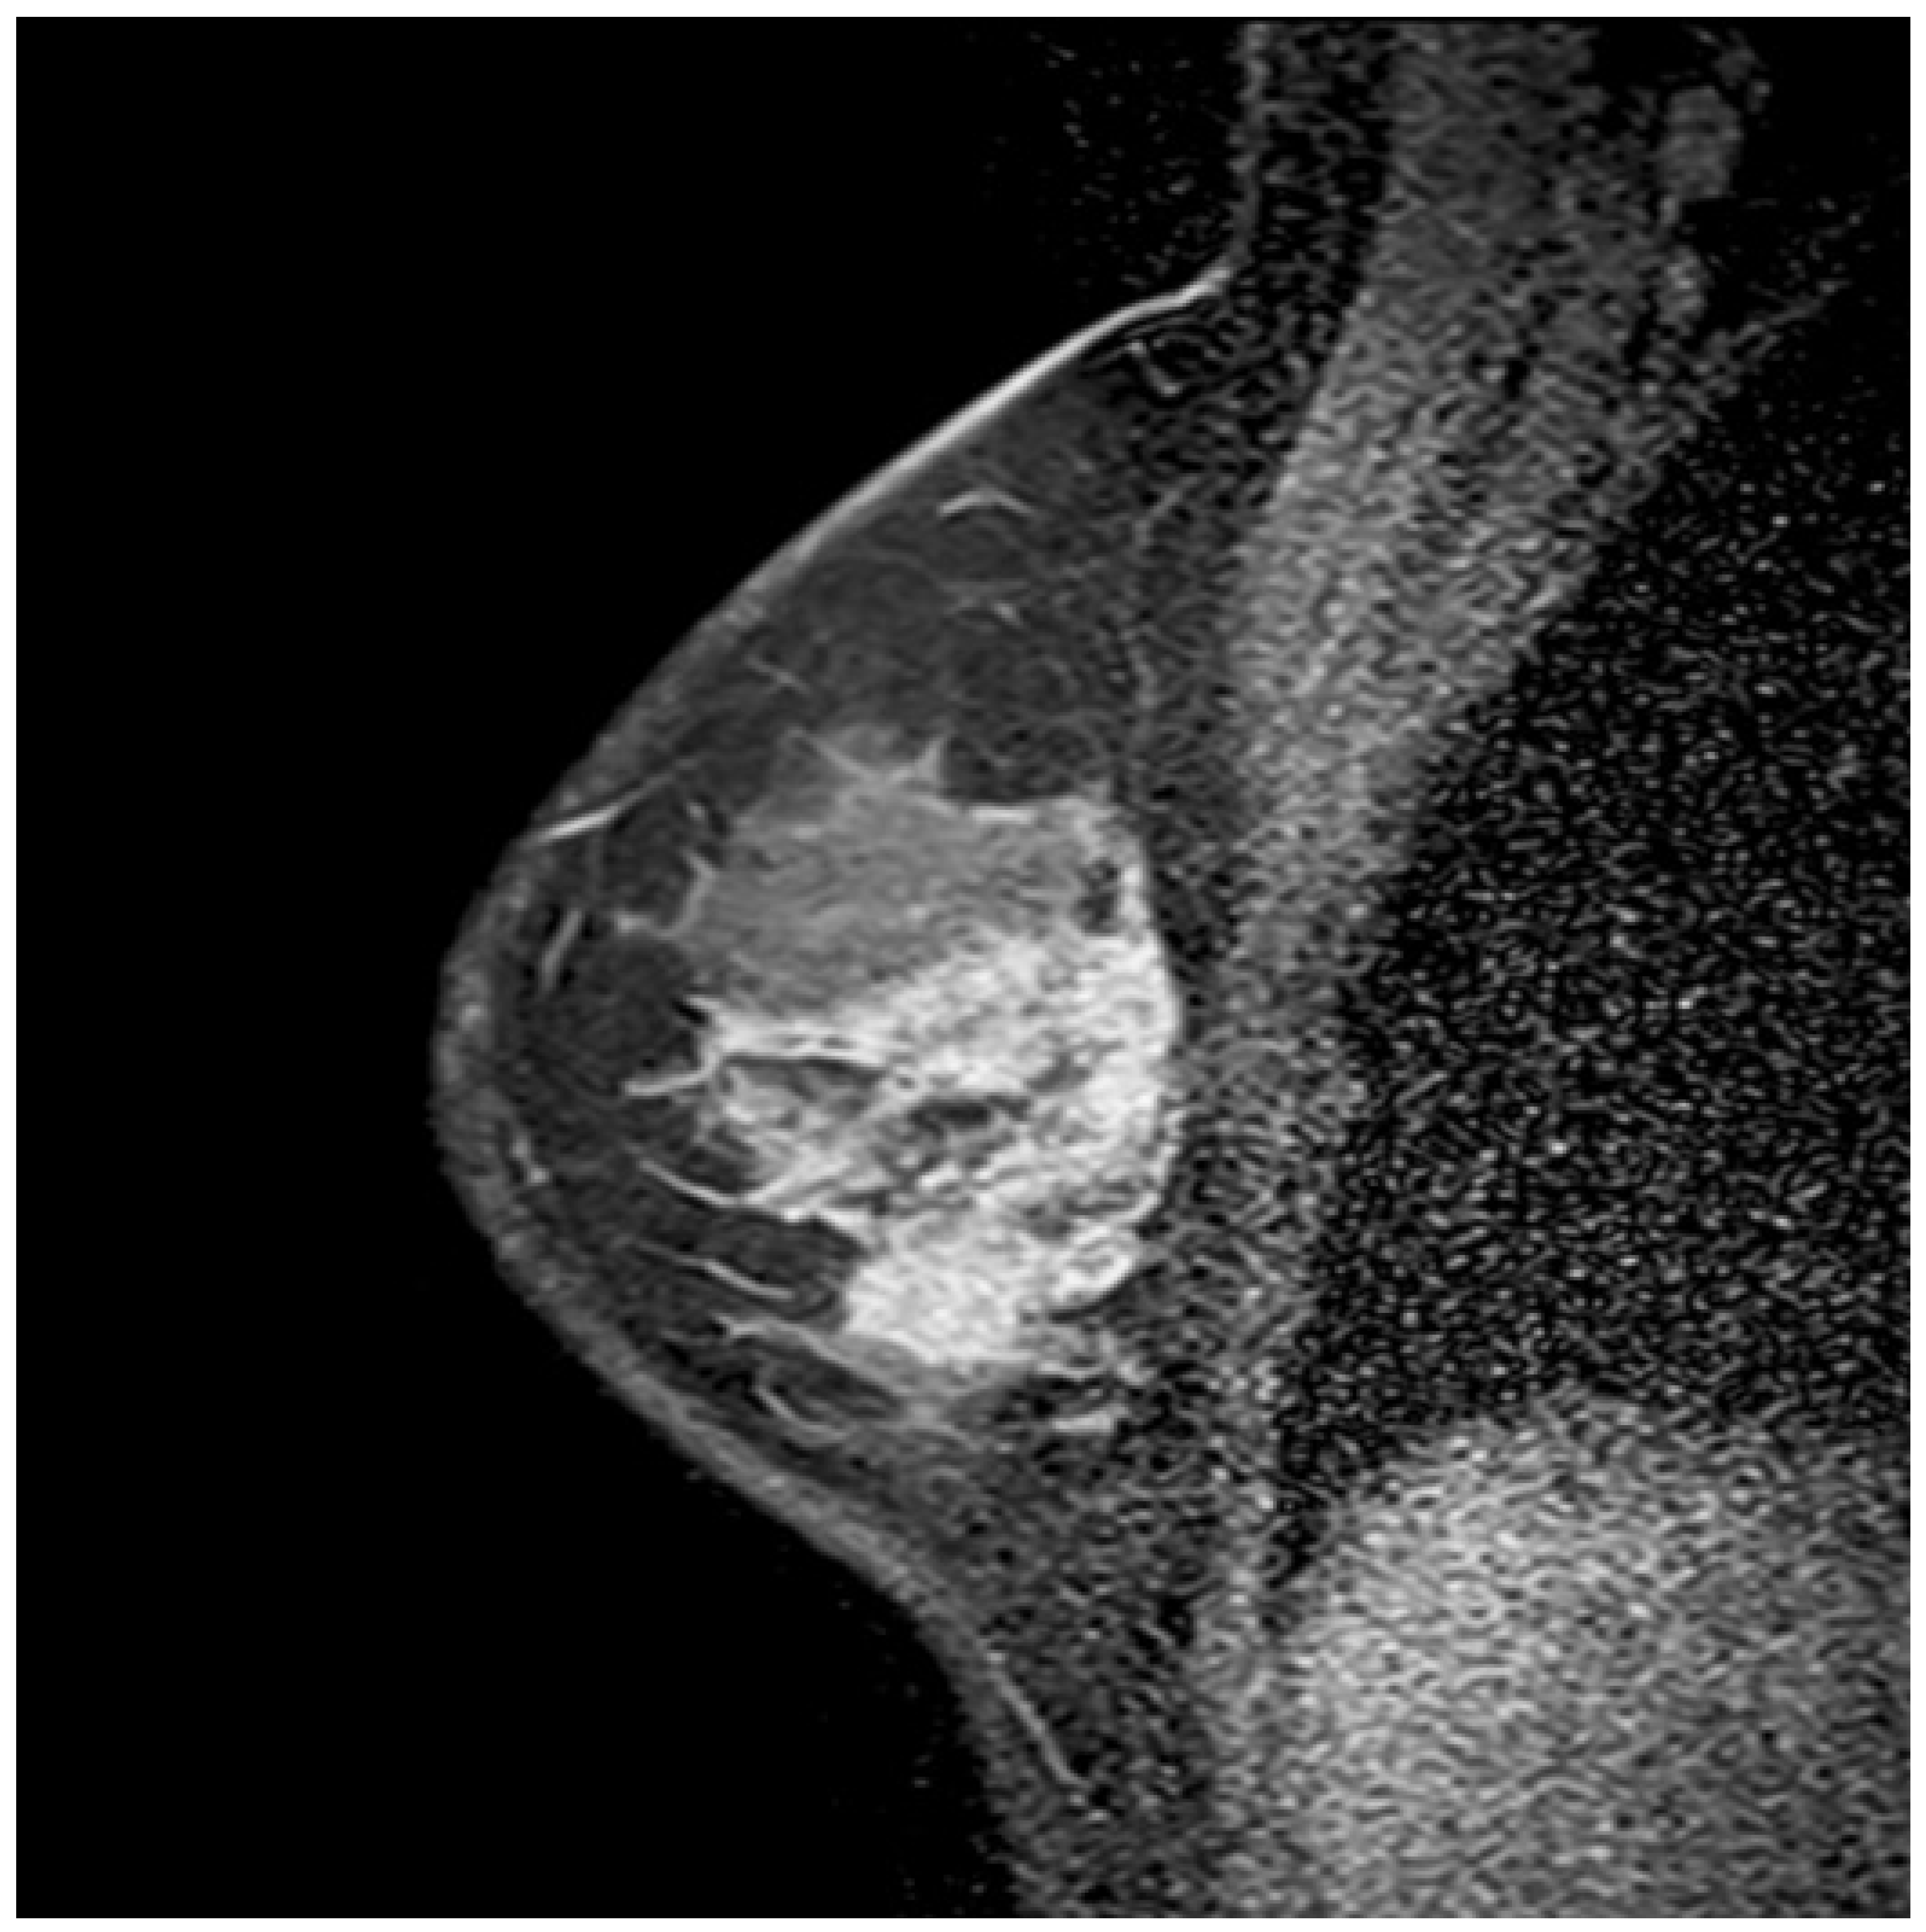

Figure 2. Breast magnetic resonance imaging of a 36-year-old woman showing segmental nonmass enhancement with a heterogeneous internal enhancement pattern. Both clumped and clustered ring enhancement features are observed. Histopathological examination confirmed the coexistence of invasive ductal carcinoma and ductal carcinoma in situ.